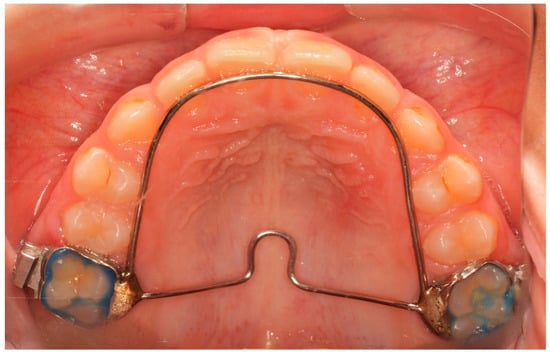

The Hyrax screw remained passive during a 6-month retention period after expansion. Until then, neither fixed nor another orthodontic appliance was used. After the passive period, the Hyrax was removed and replaced by a horse-shoe-type transpalatal arch that was used as a retainer, extending to the palatal surface of the incisors (Figure 2). This type of retainer remains in place until all permanent teeth erupt.

Figure 2.

Horse-shoe-type TPA used after T2 time interval.